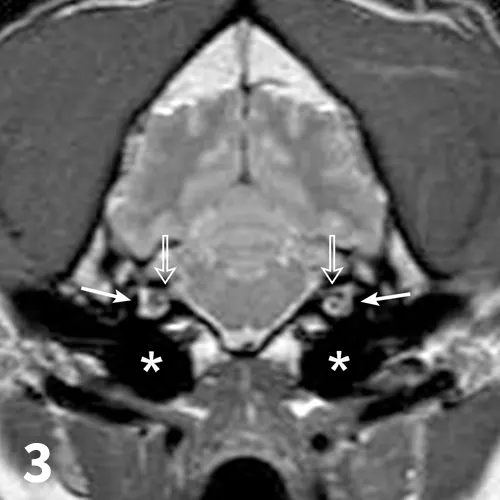

Figure 3.A transverse plane, proton density MRI at the level of the medulla and rostral cerebellum of the patient. The normal facial and vestibulocochlear nerves are seen exiting the internal acoustic meatus (open arrows). Normal cochlea are seen bilaterally (solid arrows). The normal tympanic cavities are filled with air (asterisks).

During general anesthesia for the MRI, the patients narrowed palpebral fissure, deviation of the nasal planum, and abnormal ear position resolved (Figures 2 and 3). On recovery from anesthesia, the abnormalities returned. This confirmed HT1,2 and excludes from consideration denervation atrophy (contracture), as relaxation of the muscles under anesthesia would not occur.